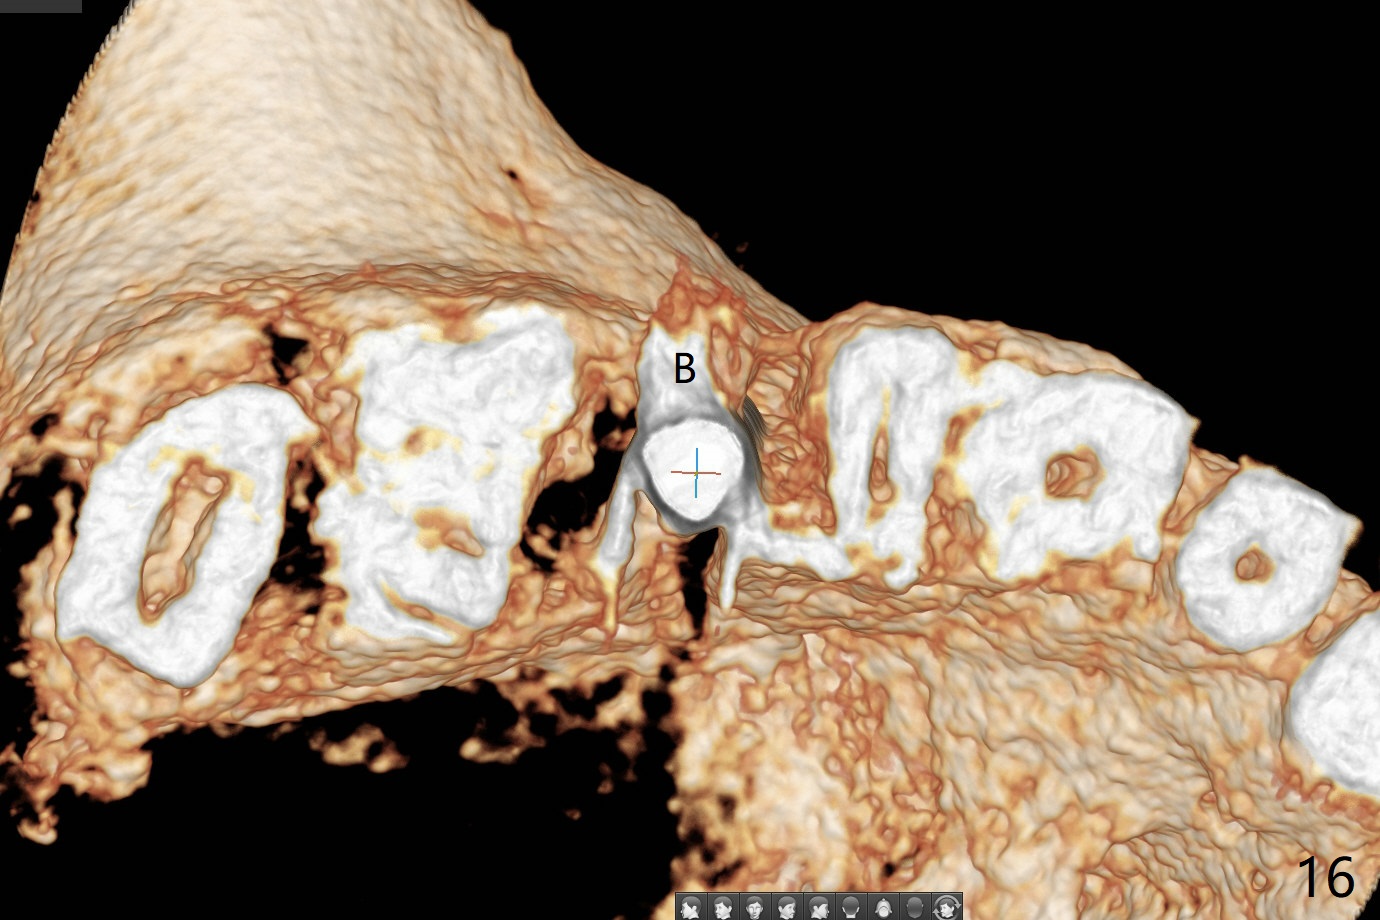

In fact there is a small buccal fistula, which is communicated with the underlying implant threads. Although preop CT shows that the buccal crest is lower than the palatal (3.8x13 mm, Fig.10 P) one, intraop finding of missing buccal plate should dictate a shorter implant (Fig.11) or onlay graft to avoid periimplantitis. Regeneration of the bone plate is limited. Later the fistula disappears with formation of a concavity (Fig.13). There is no symptom. Is bone graft necessary with a remote incision? 3-D images of CT taken 1 year 5 months post cementation show possible mesiobuccal and distopalatal bony defects (Fig.13-16). It is possible that bone graft was placed enough palatal (Fig.16). DO composite at #3 is redo satisfactorily (Fig.17 *).